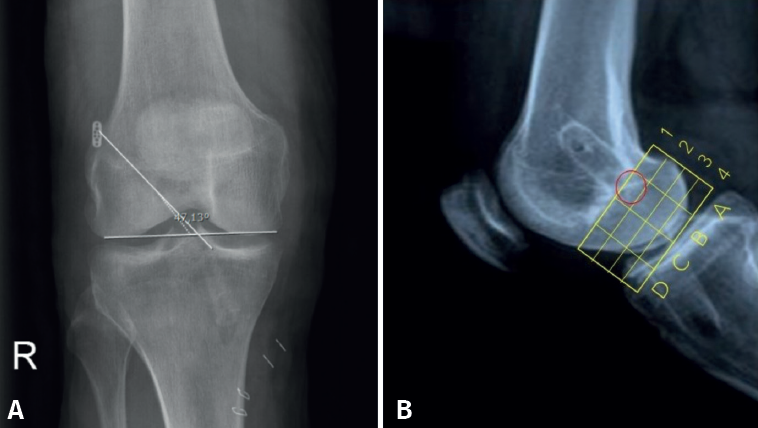

El posicionamiento del TF se evaluó mediante dos proyecciones radiológicas realizadas un mes después de la intervención: una proyección AP y otra de perfil (P) a 30° de flexión. El aparato de rayos Siemens Ysio® S y Siemens Axion Aritos® MX/VX se utiliza a una distancia de 1,5 metros. Las mediciones se realizaron con el programa informático Raim Alma. La proyección coronal permite estudiar la orientación del TF. Se mide el ángulo formado entre la superficie articular bicondilar y el TF. Revisando estudios previos incluidos en la bibliografía, un ángulo menor de 30° o mayor de 55° se asocia con reconstrucciones insuficientes del LCA y mayor riesgo de rotura(10). La vista sagital indica el posicionamiento de la entrada del TF en el área intercondílea femoral externa. Se utiliza el método del “cuadrante femoral”(11) según el cual se toma como referencia la línea de Blumensaat (intercondílea posterior), que sirve de guía para elaborar el eje de coordenadas que se muestra en la Figura 4A.

Paralelamente a la línea de Blumensaat, se traza otra línea a nivel de la superficie articular y este espacio se divide en 4 zonas horizontales del mismo grosor mediante otras 3 líneas paralelas. Los 4 espacios obtenidos constituyen el eje de ordenadas y se numeran de proximal a distal con los números 1, 2, 3 y 4.

Perpendicularmente a la línea de Blumensaat y con la superficie articular anterior y posterior como límite, la superficie se divide en 4 espacios de igual longitud. Estos espacios constituyen el eje de abscisas, que se identifican de posterior a anterior con las letras A, B, C y D. El correcto posicionamiento del TF para la inserción femoral del LCA corresponde al área delimitada según este eje de coordenadas del método del cuadrante femoral con los valores B1 y B2 que se muestran en la Figura 4B. El principal resultado radiológico fue la posición del TF, que se llevó a cabo mediante dos proyecciones radiológicas un mes después de la intervención: una proyección AP y una P a 30° de flexión. La proyección AP se utilizó para medir el ángulo formado entre la superficie articular bicondilar.

La proyección sagital se utilizó para determinar la entrada del TF en el área intercondílea femoral externa y se representó mediante coordenadas del método del cuadrante femoral.